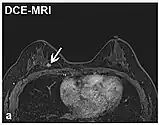

| Realce de contraste dinâmico | DCE | Medidas de mudanças ao longo do tempo no encurtamento da relaxação spin-lattice (T1) induzido por um bolo de contraste de gadolínio.[82] | O aumento rápido do contraste de gadolínio, juntamente com outras características, sugere malignidade. [83] | ![]() | |